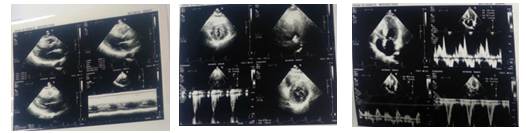

肥厚型心肌病改良扩大Morrow术后,左室流出道较为通畅,左室流出道压差基本正常,运动激发试验阴性。室间隔厚度为17mm。静息状态下压差为9mmHg,运动后压差为23mmHg。